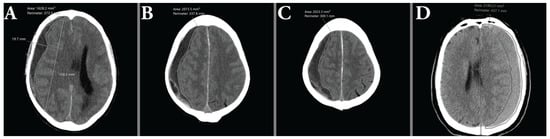

2.7. Hematoma Volumetry

2.8. Hematoma Characterization

2.9. Uni- and Bilateral Hematomas

3.2. Comparison of Manual Measurements of Hematoma Volume with the ABC/2 Method